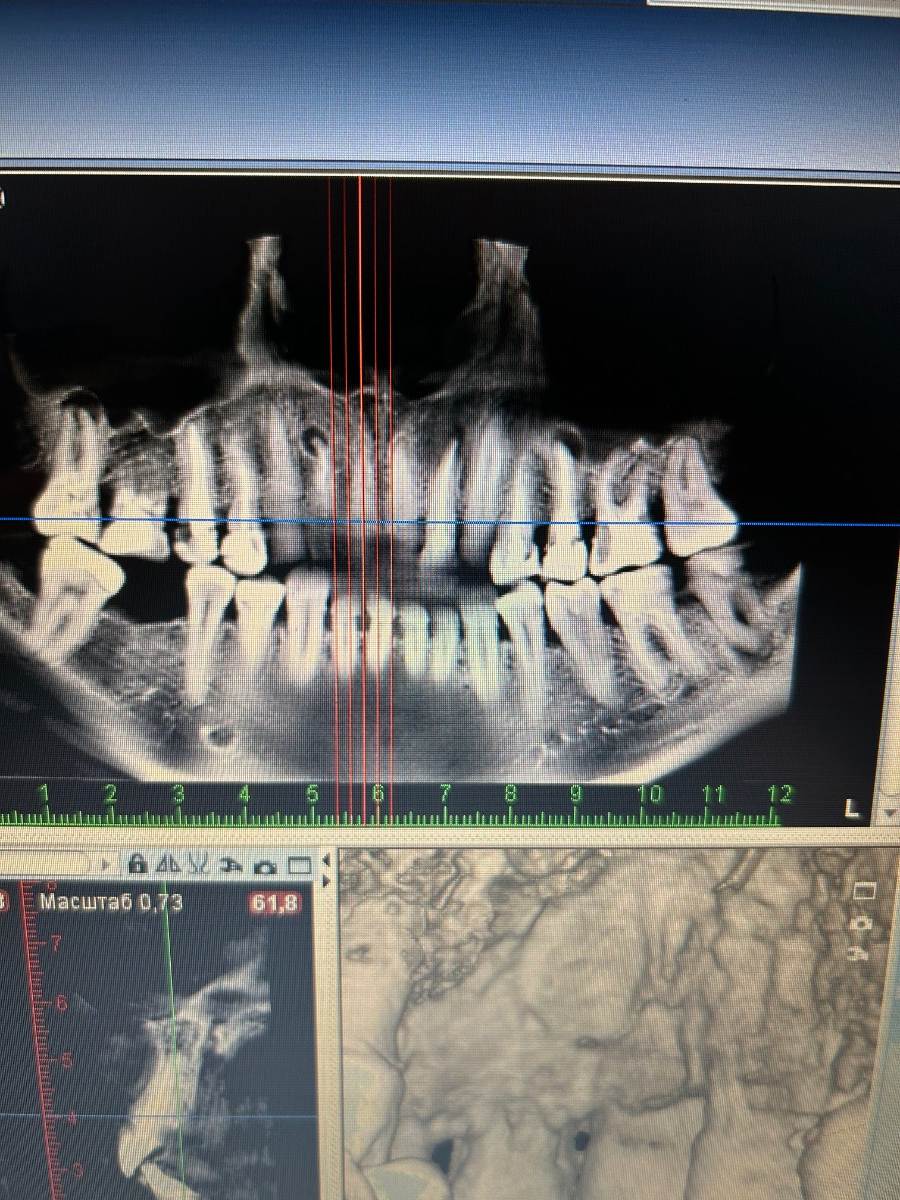

Добрый день. Заболела правая верхняя часть челюсти. Сделали 3д снимок, все зубы депульпированы, кроме 1. Удалила семерку с большим воспалением, перелечивать не было желания. Боль осталась. Депульпировали тройку, заложили витапекс. Далее  перелечивали двойку с воспалением, также заложен витапекс+ за верхушку корня  выведен. Легче не стало, после витапекса вообще стало болеть сильно. Далее планируют убрать кариес в пятерке. Ранее ни двойка и ни тройка не болели, на нажатие, холод, тепло никакие зубы не реагируют.

Снимок прикладываю, на снимке больная сторона слева сверху, может ли кариес под пломбой пятерки давать такую боль, хотя нажимать не больно?